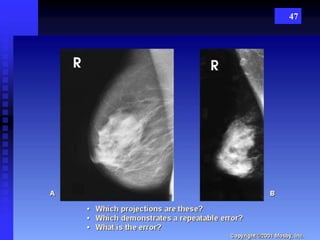

47

38 Routine Images - CC - cranio caudad  MLO – mediolateral oblique Additional view  “True” Lateral view  Latero-medial oblique view  Paddle compression view  Magnification view  Tangenital view  Cleavage view  Axillary view POSITIONING